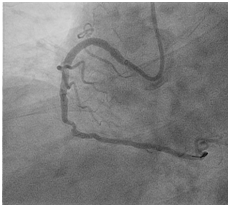

A 66-year old male with long standing history of type 2 diabetes, hypertension, dyslipidaemia and ischemic heart disease with prior history acute myocardial infarction treated with primary PCI to LAD with 3.0x22 mm drug eluting stent. Came for a staged PCI for a significant proximal RCA lesion. Following obtaining an informed consent and reload with 300 mg of Plavix. Right radial approach was selected patient received 7000 units of heparin. A 3DRCguidingcatheter was used to intubate the RCA following failure to engage with Judkin 4 guiding catheter, BMW wire advanced all the way to the distal end of RCA, lesion predilated by2.5x15mm compliant balloon to 12 atmospheres (Figure 1). A 3.5x 22mm Xience expedition stent was placed across the lesion under fluoroscopy. It was noted that the guide was not stable. It was decided to deploy the stent with the first fluoroscopy the stent appeared to have dislodged into the ascending aorta with the wire (Figure 2). Now the stent with an inflated balloon the guiding catheter and the wire all hanging in the ascending aorta. The initial decision to remedy this was to carefully and slowly withdraw the entire system along the course of the subclavian system and deploy the stent in a safe spot (Figure 3). But because of tortuosity it was thought to snare the entire system through a large femoral sheath. An 8 Fsheath was inserted into the right femoral artery and a 6 F ensnare system taken to the ascending aorta and grabbed the inflated balloon (Figure 4) and stent slowly moved down into the abdominal aorta under fluoroscopy. Then the balloon was deflated slowly and the snare tightened across the stent (Figure 5) and taken outside the body through the 8 F sheath (Figure 6) post snare femoral angiogram showed no injury to the femoral artery and a successful snaring of the dislodged stent. Patient was brought at alater date for a successful direct PCI to the RCA. This time the guide selected was an Amplatzer 0.75 (Figure 7).

Figure 2 Dislodged stent with an inflated balloon in the ascending aorta.